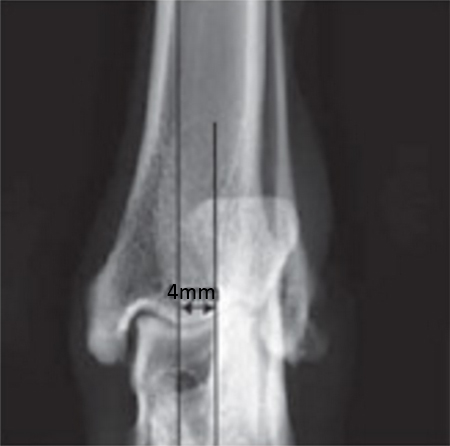

2-years-old Labrador Retriever, 30 kg, female. Chronic lameness in both hind limbs, chronic bilateral cranial cruciate ligament tears, with subsequent stifle joint instability and degenerative joint disease. At that time, she was more clinically lame on the left hind limb, and a surgical correction was subsequently performed on this limb. X-rays of the stifle joint revealed the degenerative joint changes and an effusion; the tibial plateau slope was 20. In addition, the x-rays confirmed that there was a slight amount of tibial torsion that also was observed clinically, accounting for a slight internal rotation of the distal limb. Radiographically, this could be assessed by a 4 mm shift of the normal point of intersection of the medial aspect of the calcaneus with the deepest point of the talar sulcus.